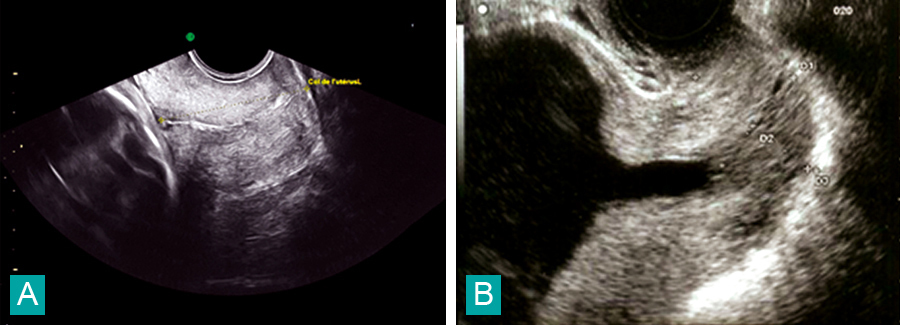

Charlotte Laplane, Claude d’Ercole (La Revue du Praticien) Écographie du col :A. Col normal.B. Col raccourci.